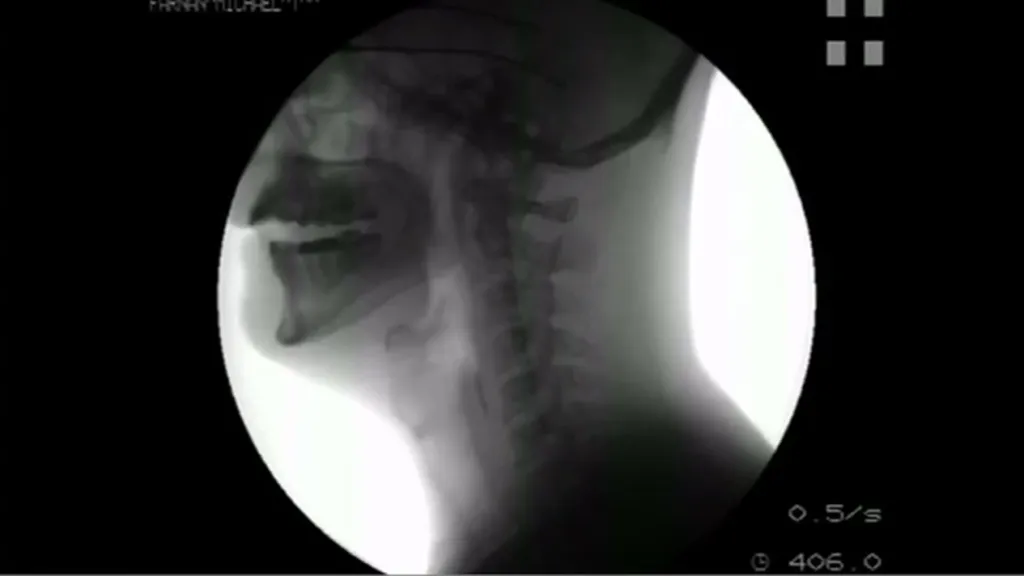

Rakovinu hlasivek lze zjistit pomocí takzvané videokymografie (VKG), což je metoda, při níž se kmitání hlasivek snímá kamerou. Rakovina se totiž projevuje tuhnutím tkáně a postupnou ztrátou schopnosti kmitat.

Výsledky z VKG je potřeba vyhodnotit, teprve poté může lékař určit, jaká diagnóza je na místě. „Manuální hodnocení výsledků VKG nálezu je však obtížné a vyžaduje zkušenost, kterou lékař získává řadu měsíců. Proto bylo potřeba vyvinout sofistikovaný software k automatickému hodnocení lékařských nálezů vysokorychlostního zobrazení kmitání lidských hlasivek a přiřadit jim správnou diagnózu,“ uvedla Jitka Vydrová, vedoucí lékařka společnosti Medical Healthcom, která se na vývoji softwaru podílela.